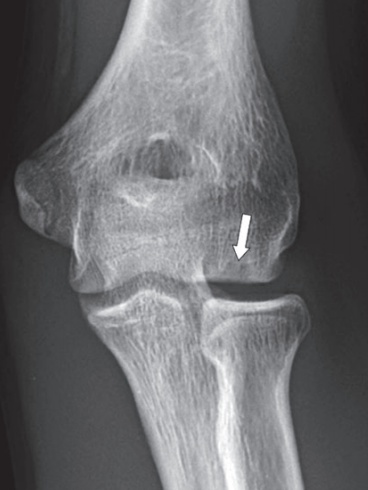

对于一些软组织的显示,尤其是骨折周围韧带、肌肉以及软骨的损伤程度,MRI有显著的优势。比如这位外伤病人,他的MRI图像能明确地诊断剥脱性骨软骨损伤。

(同一患者的X线片与MRI图)